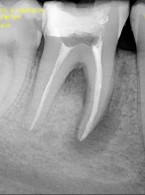

Leczenie endodontyczne zęba 46 z przewlekłym ropnym zapalaniem tkanek okołowierzchołkowych – opis przypadku

Aneta Bartoszyńska, Aleksandra Kobierzycka